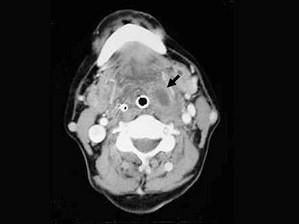

问题 患者,男性,23岁,发热头痛3天,伴咽旁和颈部剧痛,吞咽困难,吐字不清,查体:扁桃体及咽侧壁突向咽腔,但无明显充血,CT检查结果如下图:患者最可能的诊断为 ( )

选项 A、咽后脓肿 B、以上都不是 C、扁桃体周脓肿(前上型) D、扁桃体周脓肿(后上型) E、咽旁脓肿

答案 E